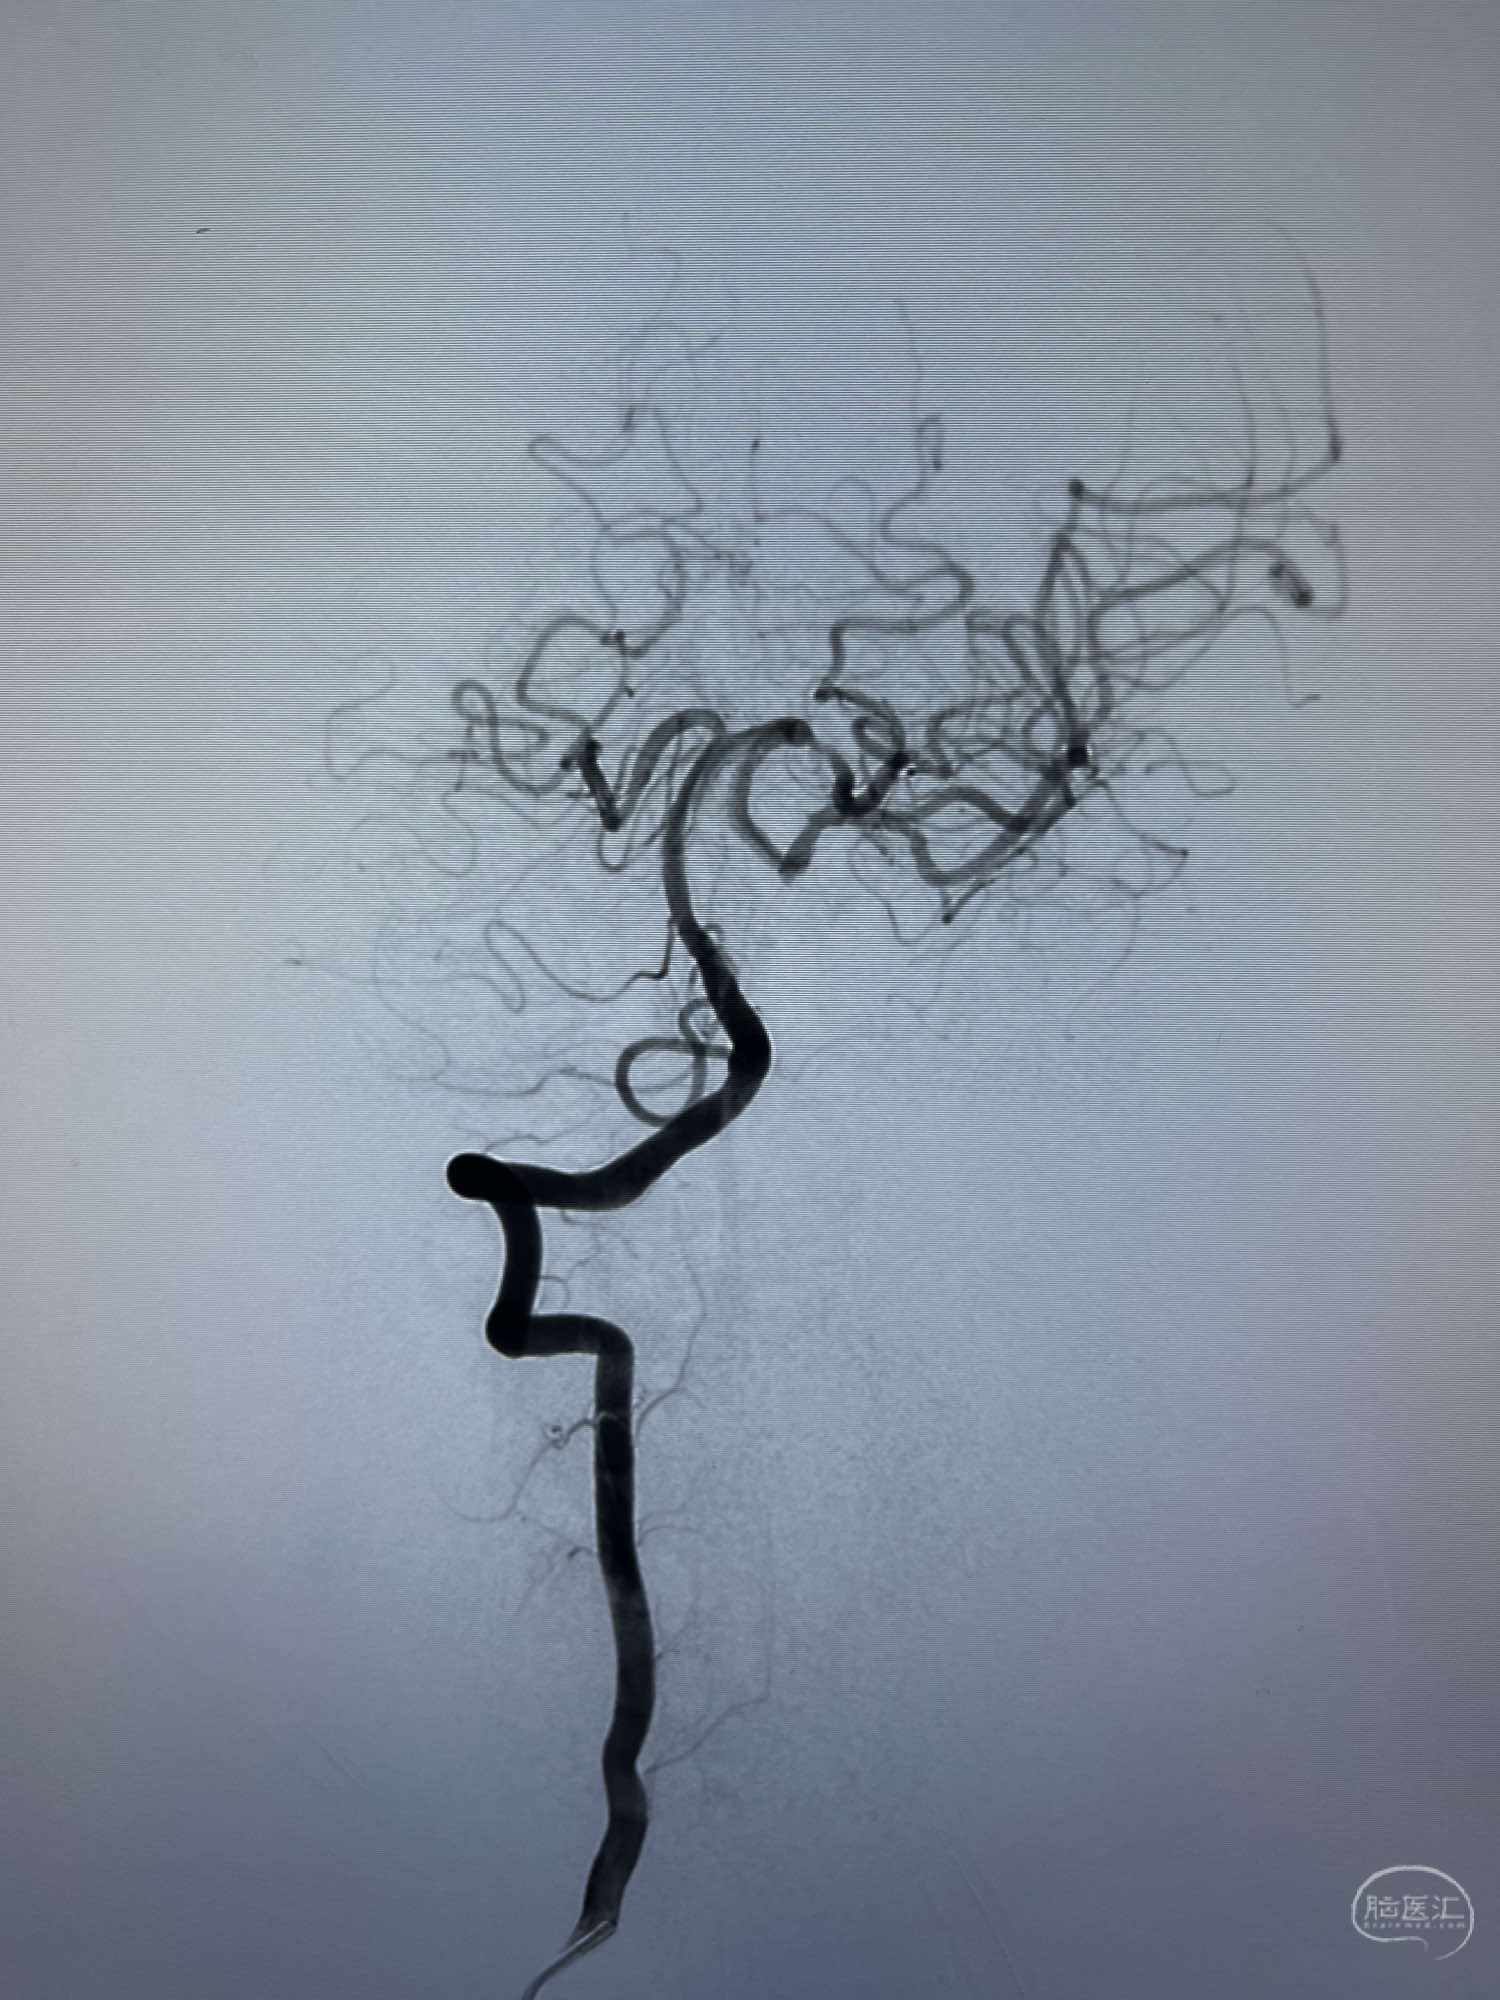

DSA示:左侧颈内动脉眼动脉段以远闭塞,后交通动脉开放,椎基底动脉通过后交通动脉代偿左侧大脑中动脉区域,右侧发出双侧大脑前动脉,右侧大脑中动脉M1末端宽颈动脉瘤,大小约4.3mmx4.6mm。

6F Neuromax➕6F115cm 心玮中间导管建立路径,sychro14微导丝➕VIA21超选至动脉瘤体内近中部,WEB5mmx3mm植入动脉瘤。